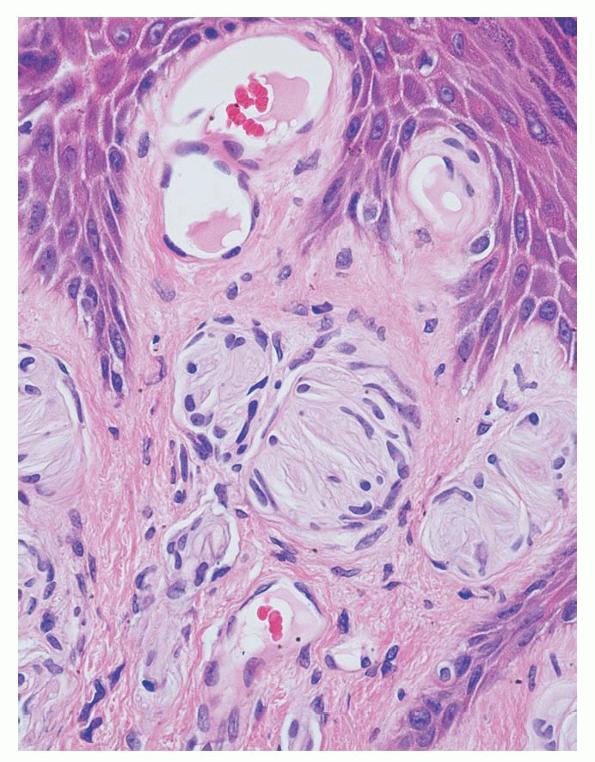

meissner-corpuscle